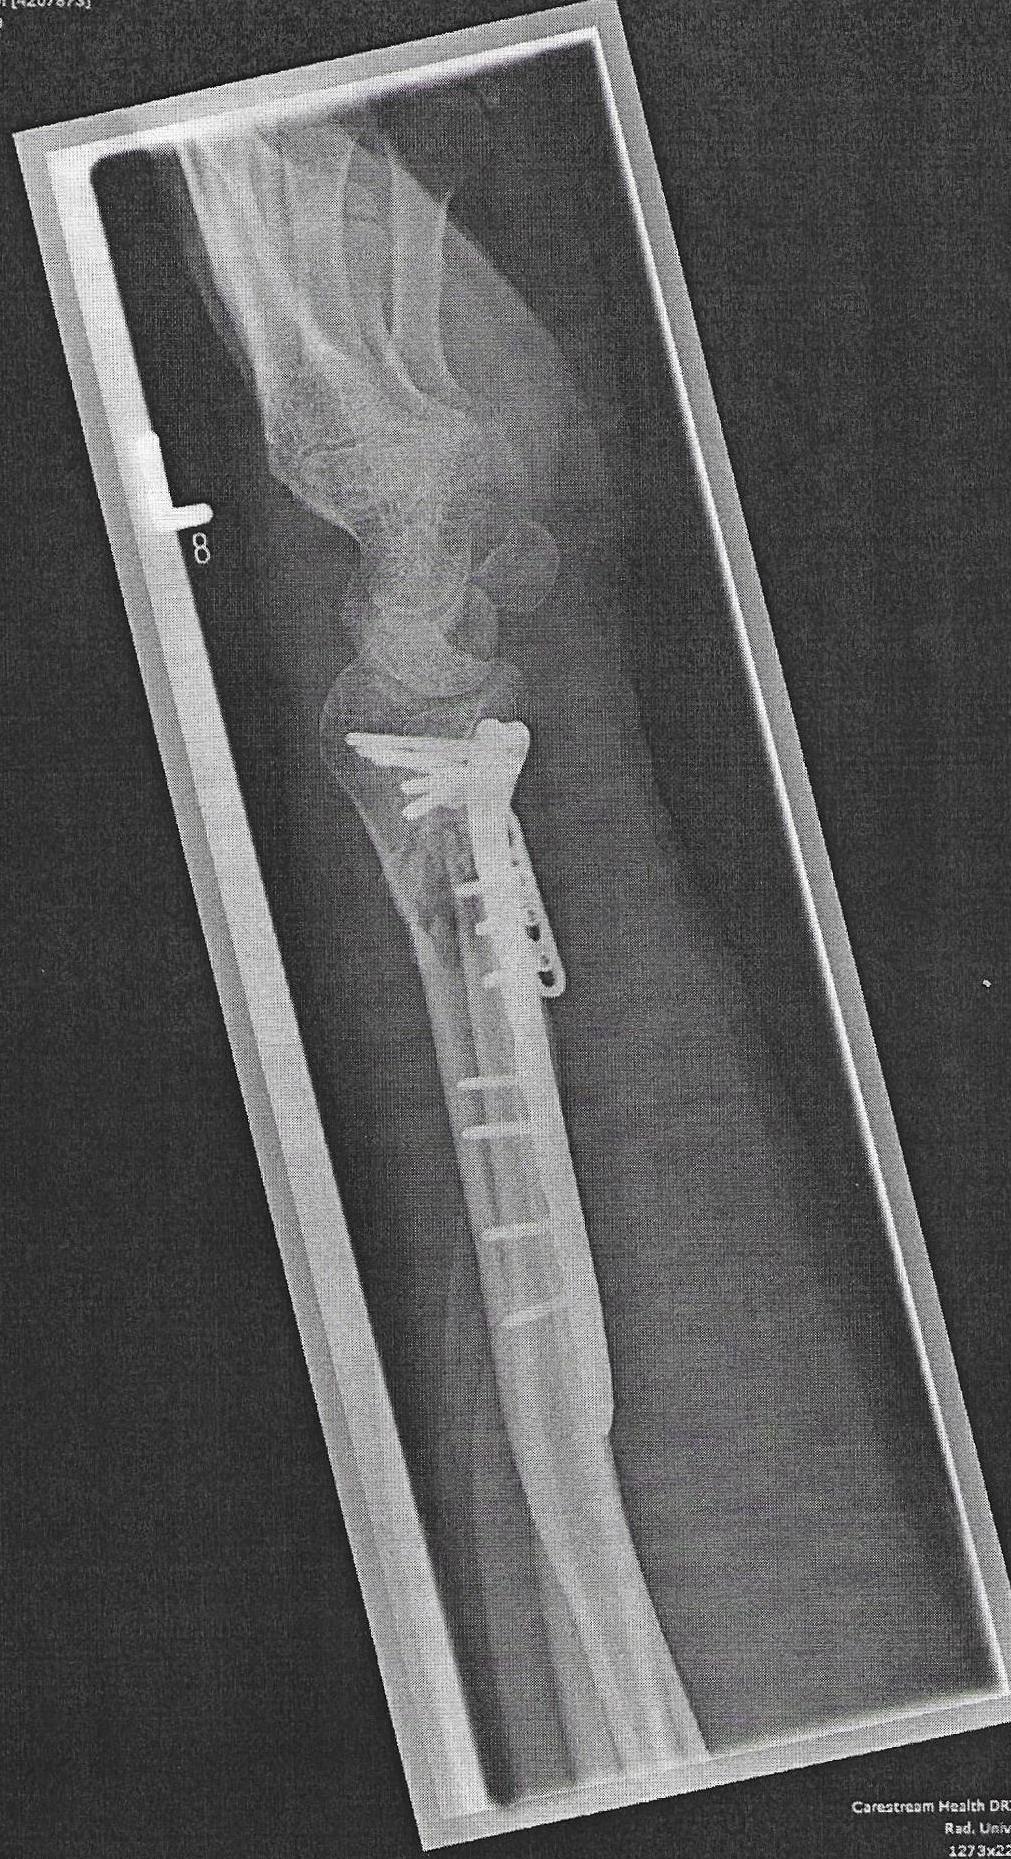

Nein, ist wirklich vergessen, dass vielleicht zu viel Gewebe zugewachsen ist, war auch 2 Jahre nach der Installation. Außerdem machen sie nicht "automatisch" ein Foto nach der OP.vergessene Schraube? die sieht man doch auf jedem billigen Rötgenbild..

Die kann ja nur absichtlich drin noch geduldet gewesen sein?

Dann haben Sie die anderen Bilder noch nicht gesehen diese sind auch hier in der Topikdas sieht ja echt überl ausSchnelle und Beste Genesung wünsche ich dir @Eddy der Belgier